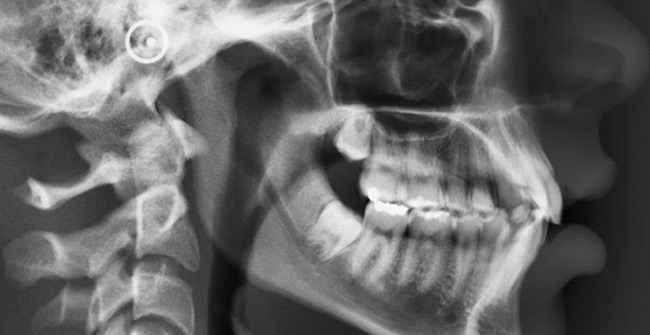

Telerradiografias (perfil e frontal)